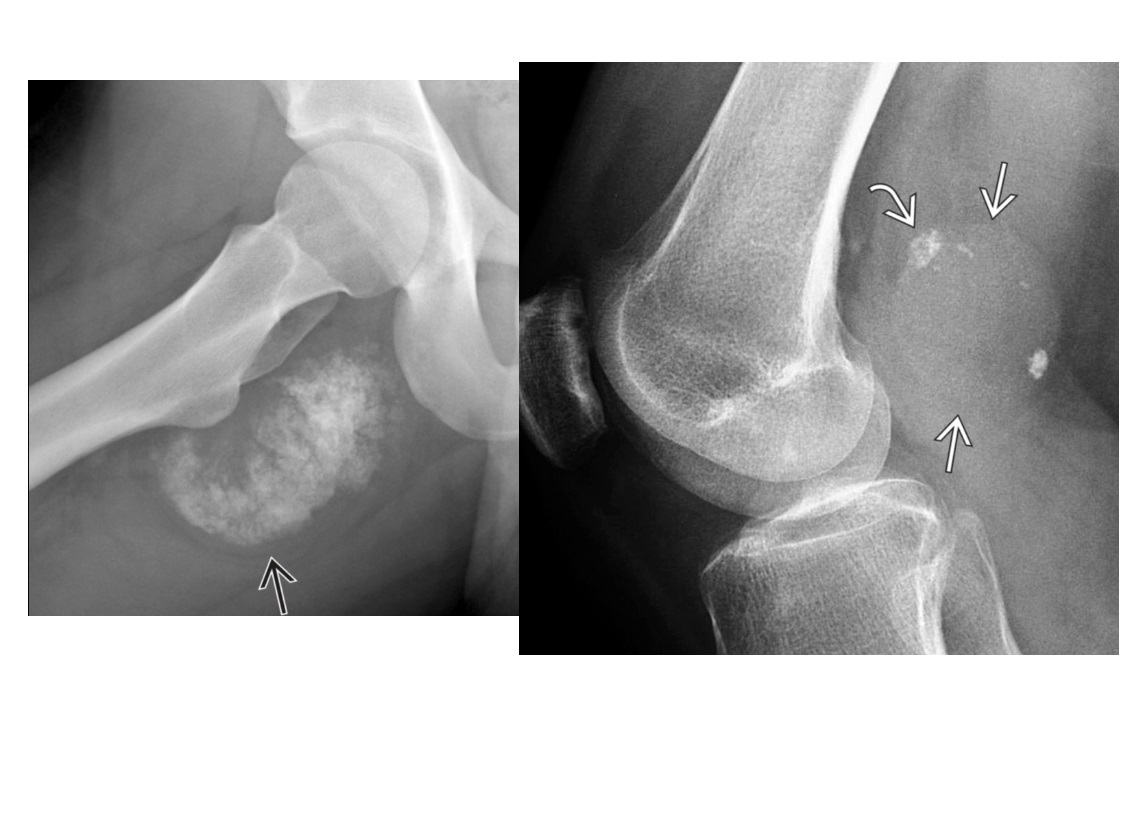

ENCHONDROMA

Commonest location Hands/feet

Long bones: proximal humerus > distal and proximal femur > proximal tibia

Intramedullary and metaphysis

multiple enchondroma

Maffuci - haemangioma

Olliers - multiple enchondroma only

DDx

-Brown tumor (hyperparathyroidism),

-sarcoid - lace like bone lesion phalanges

-intraosseous ganglion

-metastatic disease.

MRI

T1: low to intermediate signal

Fluid-sensitive sequences: lobulated high signal typical of cartilage lesions

Enhancement: peripheral and septal, accentuating lobules